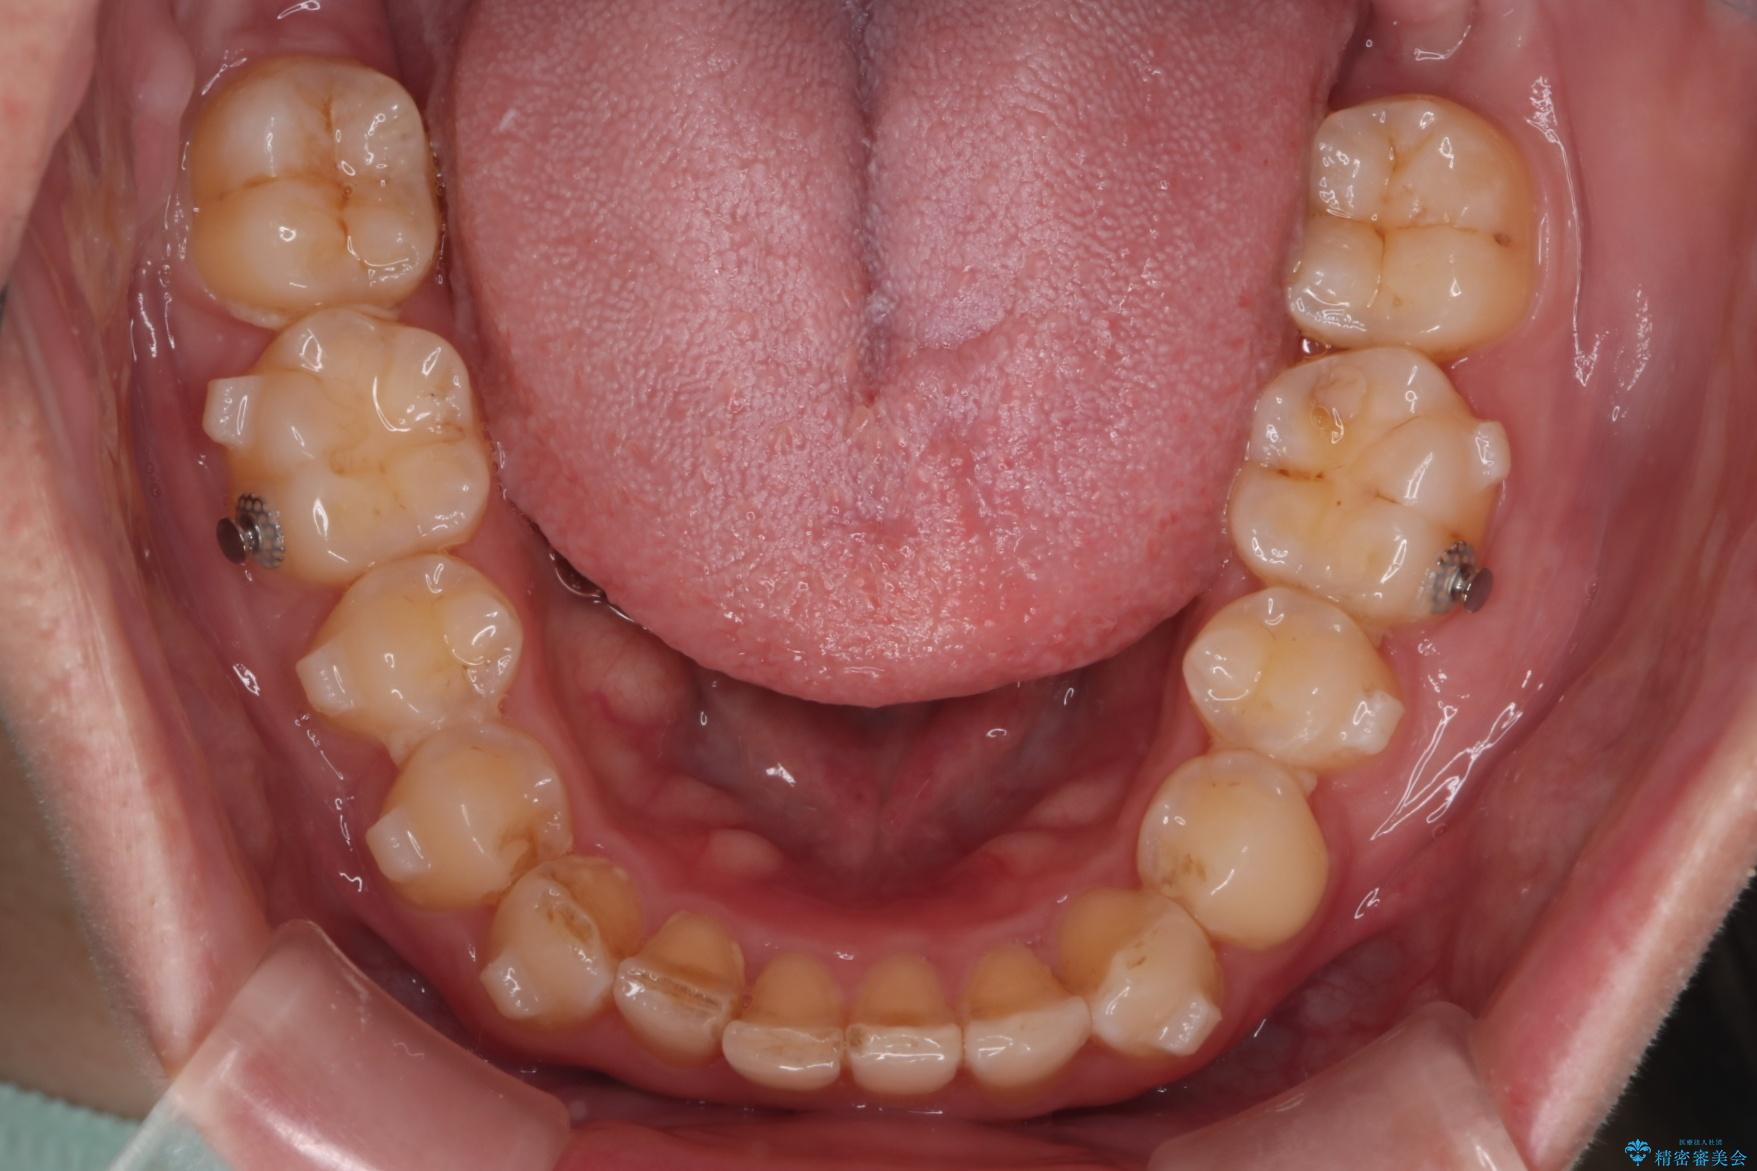

下の歯のがたつきと右の奥歯の噛みあわせ改善する治療計画を立てました。

まず右側臼歯部の咬合改善のために、臼歯部のみ部分的なワイヤー矯正を行い、咬合改善がみられてからインビザラインにて全体的な矯正を行なっていくこととします。

噛み合わせをよくするために、ワイヤー矯正とインビザライン矯正のどちらの期間も必要な箇所にゴム掛けを行いながら治療を行いました。

下の前歯のがたつき改善にはIPR(歯と歯の間を削る処置)を行いました。